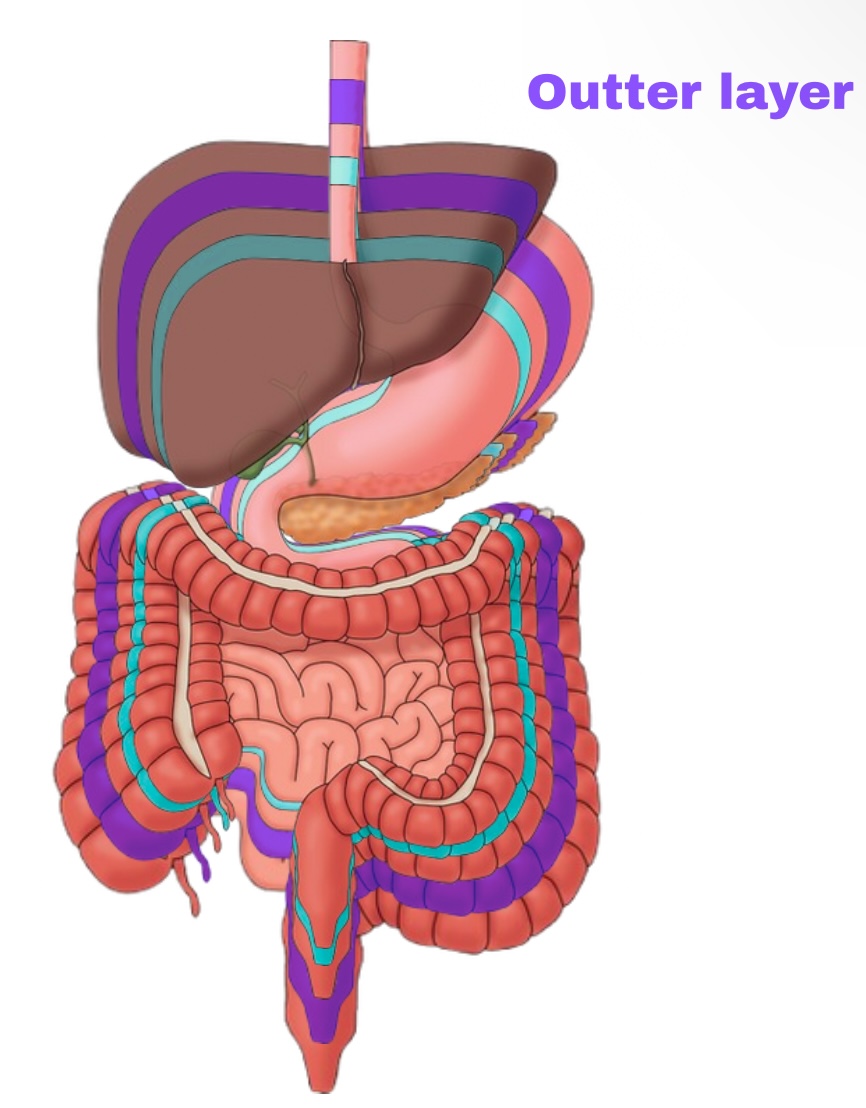

Partial Peritoneum

Outer layer

Visceral Peritoneum

Deep layer (surface of organ)